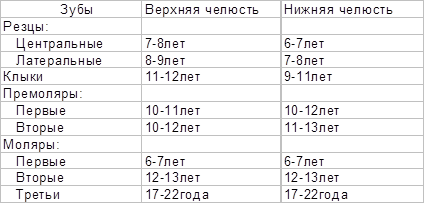

Поскольку сроки и последовательность формирования молочного и постоянного прикуса у детей достаточно определенны (таблица 2,3), их широко используют в определении « зубного возраста», который устанавливают путем подсчета числа прорезавшихся зубов и совпадения его со стандартными возрастными нормами.

Молочные зубы прорезываются с 6 мес до 2-2,5 лет и на этом отрезке постнатального онтогенеза могут служить в качестве показателя физиологической зрелости.

Таблица 2 Время прорезывания и выпадения молочных зубов (Losch P.K., цит. по: BermanR.E.,1991)

Таблица 3 Время прорезывания постоянных зубов (Losch P.K., цит. по: BermanR.E.,1991)

В молочном прикусе различают два периода. Первый длится от начала его формирования до 3-3,5 лет. В этом периоде зубы стоят тесно без промежутков между ними, стертость зубов незаметна, прикус ортогнатический в следствии недостаточного роста и вытягивания вперед нижней челюсти. Второй период (от 3,5 до 6 лет) характеризуется появлением физиологических промежутков между зубами (диастемы или тремы), значительной стертостью зубов и переходом прикуса из ортогнатического в прямой.

Смена молочных зубов на постоянные (период сменного прикуса) характеризует биологический возраст в интервале от 6 до 13 лет. В этот период выявлена корреляция зубного возраста с развитием скелета и уровнем полового созревания.